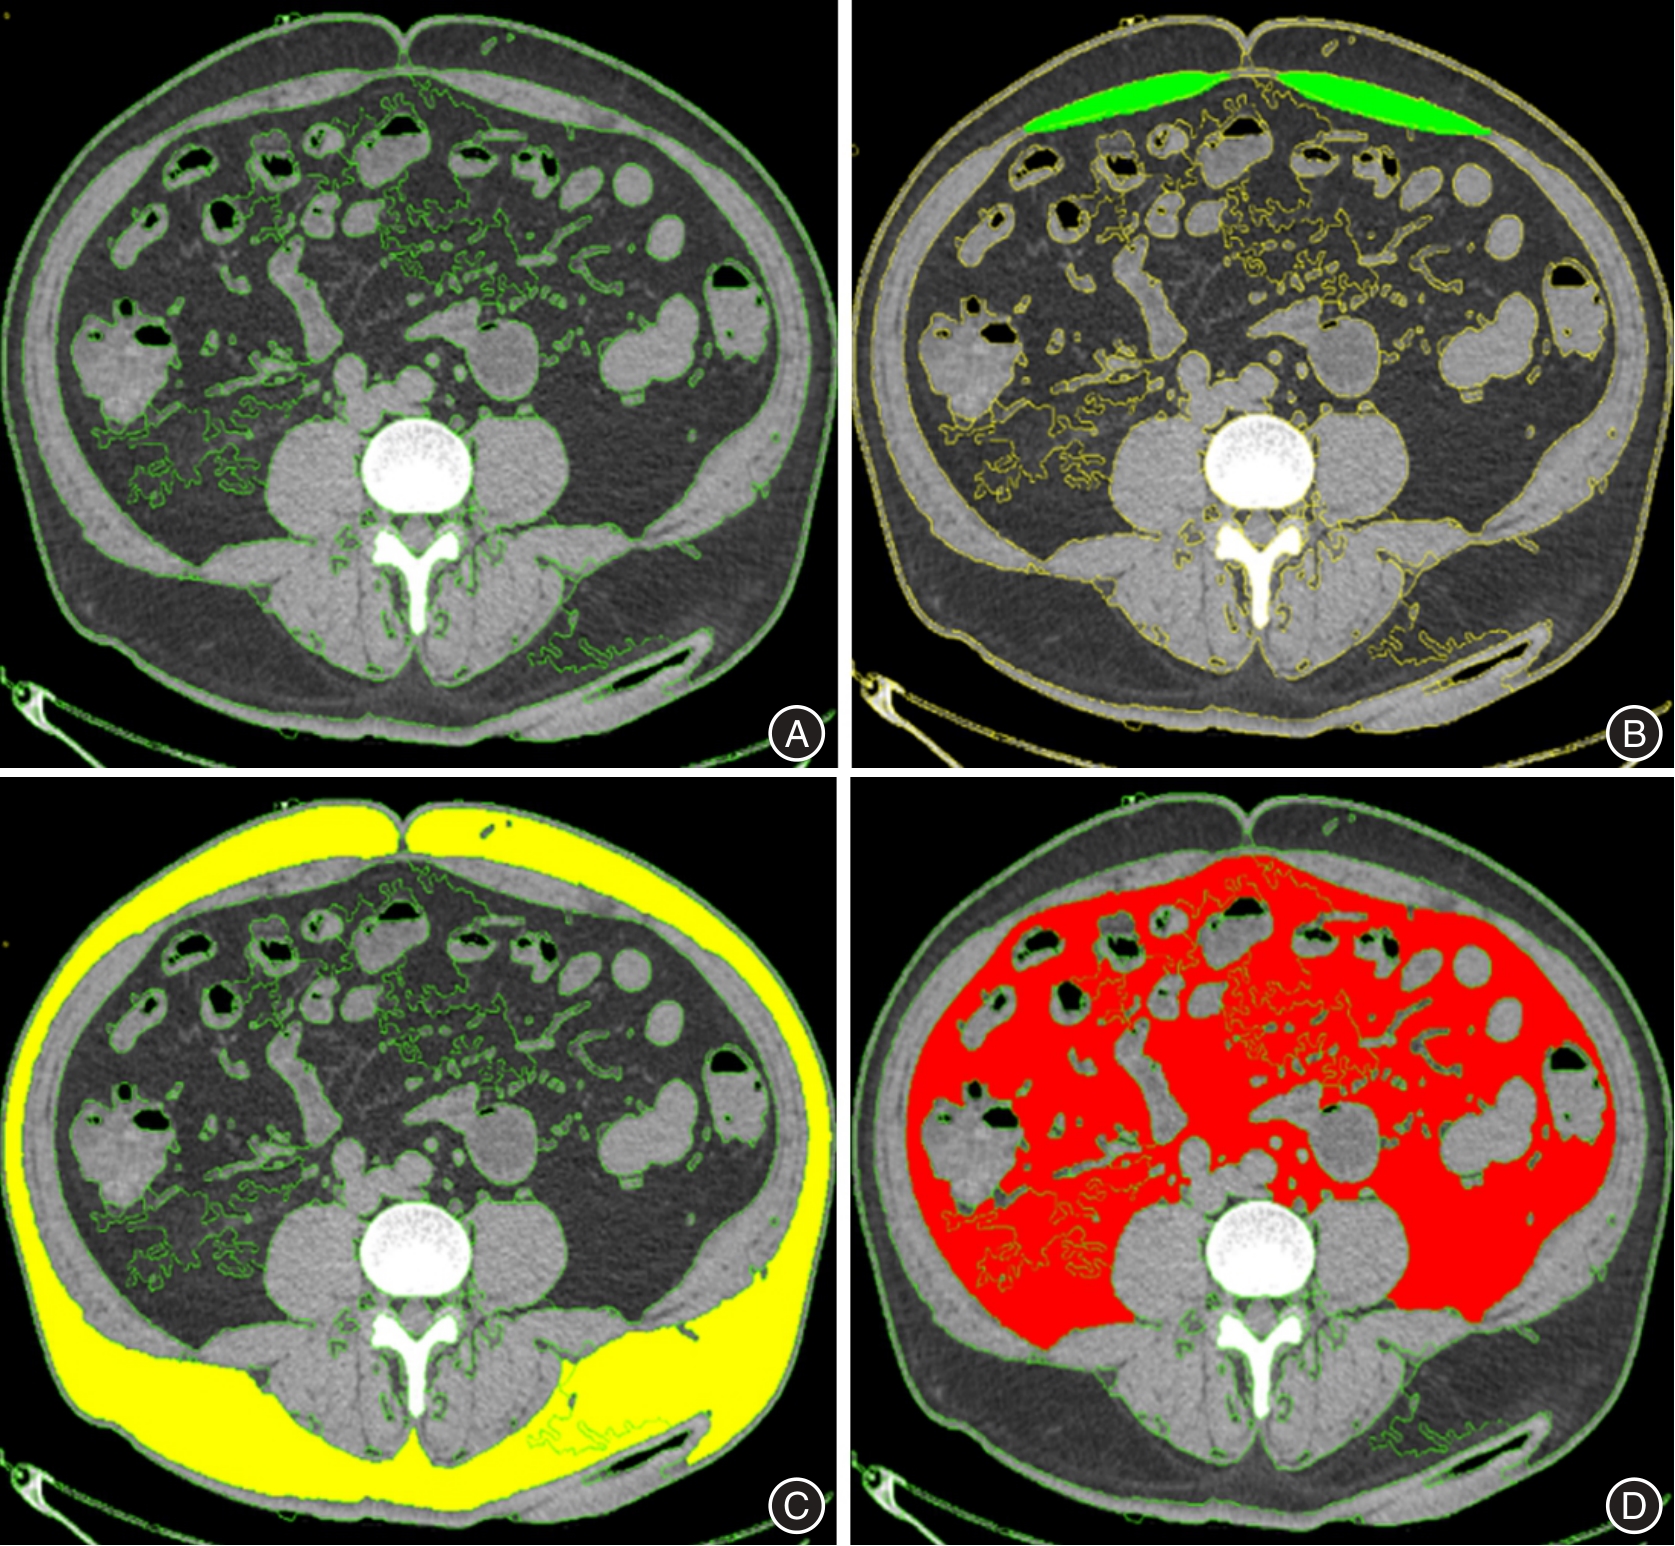

| 9 | YOSHIZUMI T, NAKAMURA T, YAMANE M, et al. Abdominal fat: Standardized technique for measurement at CT[J]. Radiology,1991,211(1):283-286. |

SHUSTER A, PATLAS M N, PINTHUS J H, et al. The clinical importance of visceral adiposity: A critical review of methods for visceral adipose tissue analysis[J]. Br J Radiol,2012,85(1009):1-10. doi:10.1259/bjr/38447238